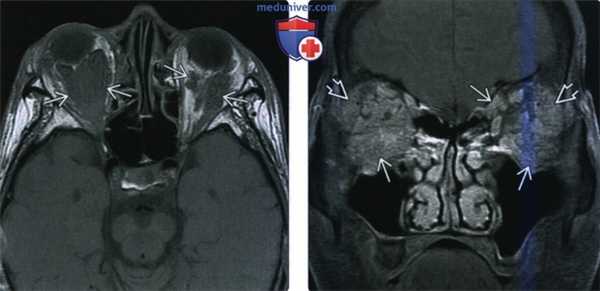

(Слева) При МРТ Т2 ВИ в аксиальной проекции отмечается выраженная гипоинтенсивность меланомы хориоидеи.

(Справа) При КТ с КУ в аксиальной проекции в заднем отрезке левого глазного яблока определяется контрастируемая опухоль с необычно крупным экстраокулярным (ретробульбарным) компонентом, вызывающим экзофтальм. Очень крупные размеры этой меланомы и экстраокулярное распространение опухоли являются неблагоприятными прогностическими факторами.